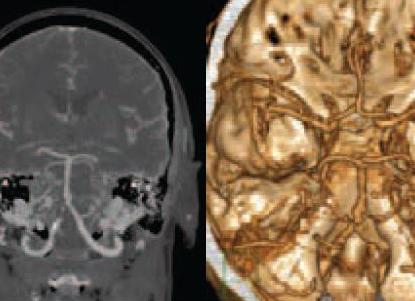

Для постановки диагноза атеросклероз интракраниальных артерий требуется провести ультразвуковое исследование, магнитно-резонансную томографию, компьютерную томографию, цифровую субтракционную ангиографию. Золотым стандартом диагностики является именно последний метод, но при этом он инвазивный, требует введения контрастного вещества. Также он предусматривает риск стойкого неврологического дефицита.

Для исключения повреждения интракраниальных артерий практикуется транскраниальная допплерография, МРТ, однако они недостаточно надежны для выявления наличия стеноза, установления его тяжести. Допплерография дает представление о состоянии коллатеральных сосудов, помогает определить цереброваскулярную реактивность.